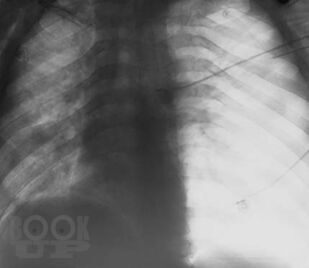

В книге изложены особенности клинической и рентгенологической диагностики повреждений и ранних осложнений закрытых травм грудной клетки. Проведен анализ объективных причин, затрудняющих основные и дополнительные методы исследования. На 240 рентгенограммах показаны признаки трудновыявляемых повреждений и осложнений травм грудной клетки, в частности пневмоторакса, гемоторакса, ателектаза, разрыва диафрагмы. Впервые отмечается клиническая значимость напряжения в малом пневмотораксе при политравме. Приведены сравнительная характеристика и алгоритм дифференциальной диагностики острых диффузных поражений легких при травме. Описан опыт выявления и решения проблемы нефункционирующего дренажа плевральной полости. Издание предназначено для хирургов, торакальных хирургов, травматологов, реаниматологов, оказывающих помощь больным с политравмой.